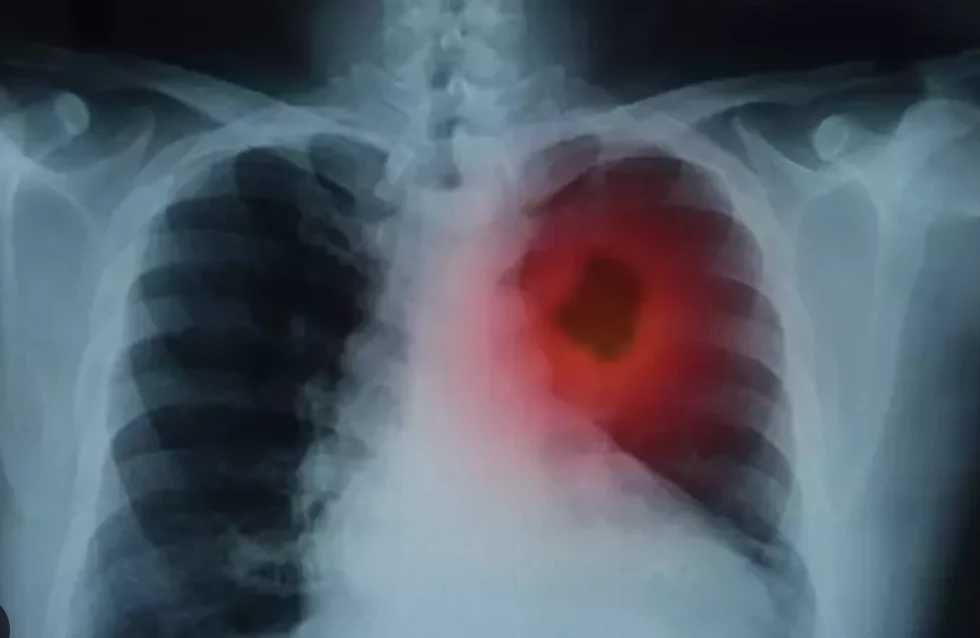

Sigaranın ciğerlerde bıraktığı zararlı kalıntılar, zamanla solunum kapasitesini düşürürken, vücudun oksijen alışverişini de olumsuz etkiler. Sigarayı bıraktıktan sonra akciğerlerin tamamen temizlenmesi kişiden kişiye değişse de, bu sürecin ortalama 1 ila 9 ay arasında değiştiği bilinir. Ancak bu süreyi destekleyici bazı doğal yöntemlerle hızlandırmak mümkündür.